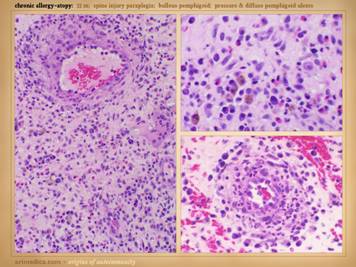

81